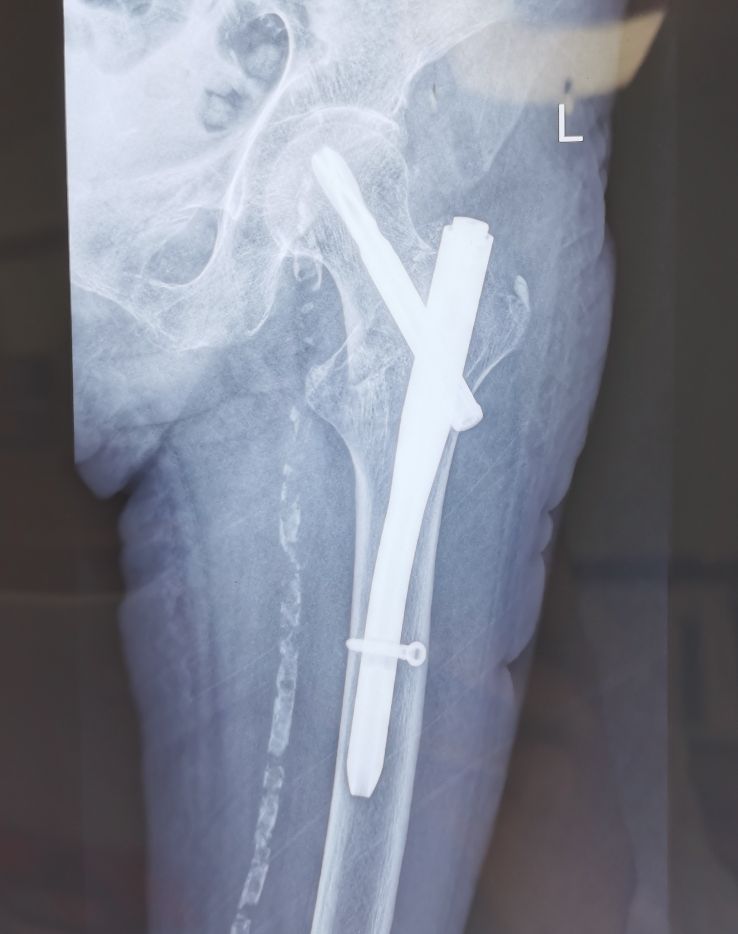

老年女性,90岁,右侧股骨粗隆间骨折术后20天入院。

这位患者属高龄患者,既往房颤及脉管炎多年,骨质疏松也特别明显。所以在康复治疗的时候,根据患者年龄,身体情况,并发症,骨质情况,手术方式,手术时间等来综合分析,给患者制定了康复方案,从床上被动关节训练,肌力训练,渐进性抗阻训练,转移训练,逐渐过渡到负重训练及步行训练,争取让患者尽早的实现下地负重步行。目前仍在康复治疗。

这个病例我是想告诉大家,高龄骨折患者的康复训练中需要考虑到的问题及因素有很多,需要综合分析来制定方案,绝对不能操之过急。